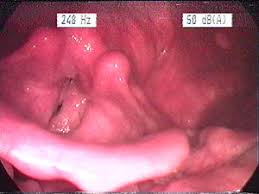

Can Tonsillitis Be Mistaken For Throat Cancer : One Singer S Sore Throat Turned Out To Be Cancer Moffitt / Tonsillitis can be caused acute infection of the tonsils, and several types of bacteria or viruses (for example, strep throat or mononucleosis).. Oral cancers can be trickier than others to recognize because the symptoms can be mistaken for other health conditions like a cold, a sore throat, or a toothache. Palatine tonsils on the sides of the throat. This rare form of oral cancer has symptoms that could easily be mistaken for a viral or bacterial throat infection. Human papillomavirus (hpv) is a common sexually transmitted infection that increases the risk of certain types of throat cancer. Symptoms of advanced tonsil cancer can include:

This Woman S Sore Throat Was Actually A Symptom Of A Rare Form Of Cancer from hips.hearstapps.com Some symptoms of throat cancer are specific to certain areas of the body. The reason for such a high prevalence rate is that people misinterpret the symptoms of throat cancer as those of tonsillitis. Swollen tonsils that are not equal in size (one is particularly larger than the other) mouth pain that does not go away. Tonsil cancer can cause difficulty swallowing and a sensation that something is caught in your throat. Throat cancer may spread locally to the lips, mouth or nearby lymph nodes. While tonsillitis is seen most. Hpv has been linked to cancer that affects the soft palate, tonsils, back of the tongue, and the side and back wall of the throat. Tonsillitis can be caused acute infection of the tonsils, and several types of bacteria or viruses (for example, strep throat or mononucleosis).

While tonsillitis is seen most. Lymphoma, a cancer of the immune system, can also present with swollen tonsils: Throat cancer may spread locally to the lips, mouth or nearby lymph nodes. The reason for such a high prevalence rate is that people misinterpret the symptoms of throat cancer as those of tonsillitis. I went to the docs on monday with an enlarged right tonsil. A sore, irritated throat or swollen, inflamed tonsils may be mistaken for tonsillitis, strep throat, or other common viral ailments. The doc said it is very abnormal and has a small growth on it. Hpv has been linked to cancer that affects the soft palate, tonsils, back of the tongue, and the side and back wall of the throat. It's freezing outside and germs spread more easily. Parents of young children are all too familiar with the symptoms of this type of tonsillitis, also known as strep throat. For instance, voice changes may be a sign of laryngeal (voice box) cancer, but they would rarely indicate cancer of the pharynx. It also causes persistent pain and white spots in the mouth — and crucially, a. Some symptoms of throat cancer are specific to certain areas of the body.

Throat cancer may spread locally to the lips, mouth or nearby lymph nodes. The family of ayisha green were devastated to learn her symptoms were actual… Coronavirus and tonsillitis can have similar symptoms, such as fever and sore throat, but cooper experts have put together a guide to help you. The throat has three types of tonsils. Tonsillitis is a contagious infection with symptoms of bad breath, snoring, congestion, headache, hoarseness, laryngitis, and coughing up blood. Men are diagnosed with tonsil cancer three to four times more often than women. This rare form of oral cancer has symptoms that could easily be mistaken for a viral or bacterial throat infection. There are two types of tonsillitis, acute and chronic. Some symptoms of throat cancer are specific to certain areas of the body. Tonsil cancer is a form of oropharyngeal cancer that occurs when the cells that make up the tonsils grow out of control and form lesions or tumors. For instance, voice changes may be a sign of laryngeal (voice box) cancer, but they would rarely indicate cancer of the pharynx. Persistent sore throat (longer than three weeks) Tonsil cancer the symptoms of tonsil cancer are similar to tonsillitis or strep throat.

Pharyngeal tonsils (adenoids) at the back of the throat. Human papillomavirus (hpv) is a common sexually transmitted infection that increases the risk of certain types of throat cancer. Another symptom is a persistent sore throat. A sore, irritated throat or swollen, inflamed tonsils may be mistaken for tonsillitis, strep throat, or other common viral ailments. The number one symptom is asymmetrical tonsils, having one tonsil larger than the other.

Faqs On Tonsil Adenoid Problems Dr Lynne Lim Ent from drlynnelim.com At first, tonsil cancer may be difficult to identify. On the other hand, tonsil cancer gives out symptoms of blood in throat, lumps in neck etc (i have already mentioned some symptoms above). Tonsillitis, or swelling of the tonsils, is usually caused by a viral infection. Hpv has been linked to cancer that affects the soft palate, tonsils, back of the tongue, and the side and back wall of the throat. Human papillomavirus (hpv) is a common sexually transmitted infection that increases the risk of certain types of throat cancer. The difference is that common health issues like a cold will begin to resolve themselves in a matter of weeks. Tonsillitis is a contagious infection with symptoms of bad breath, snoring, congestion, headache, hoarseness, laryngitis, and coughing up blood. Throat cancer may spread locally to the lips, mouth or nearby lymph nodes.

Tonsil cancer the symptoms of tonsil cancer are similar to tonsillitis or strep throat. Throat cancer may spread locally to the lips, mouth or nearby lymph nodes. It can even occur in people who have had their tonsils removed! Tonsil cancer is a form of oropharyngeal cancer that occurs when the cells that make up the tonsils grow out of control and form lesions or tumors. Compared to other cancers, throat cancer is considered to be relatively uncommon. The most significant risk factors for tonsil cancers are tobacco and alcohol use. Tonsil cancer is an abnormal growth of cells that forms in a tonsil. The reason for such a high prevalence rate is that people misinterpret the symptoms of throat cancer as those of tonsillitis. There are three types of tonsils: This time of year, coughs, colds and sore throats are common; For instance, voice changes may be a sign of laryngeal (voice box) cancer, but they would rarely indicate cancer of the pharynx. Men are diagnosed with tonsil cancer three to four times more often than women. Tonsillitis, or swelling of the tonsils, is usually caused by a viral infection.